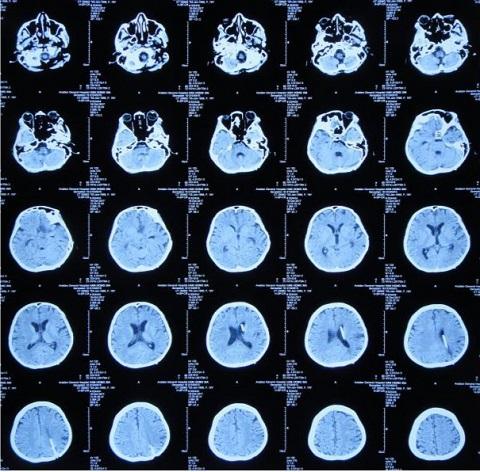

10月18日,患者脑脊液外观基本清亮,增强头MRI现实仍然课件鞍区多发结核脓肿、四叠体池、环池内病变明显改善。

10月20日,行分流手术,术后复查增强头MRI见图。